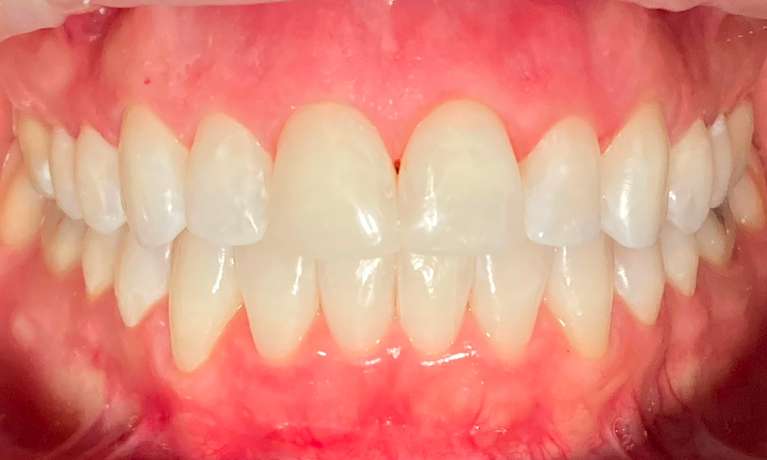

This case combined Invisalign, composite restorations, whitening and veneers to restore damage done from decades of grinding. Most dental offices would have placed crowns on all the back teeth, but with Invisalign treatment to set the bite, we were able to preserve more of the patients teeth while saving time and expense.